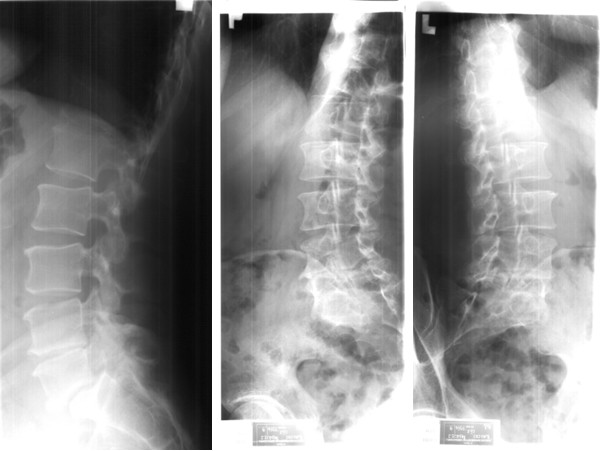

Przedstawione poniżej badania radiologiczne (rtg boczne i skośne kręgosłupa lędźwiowego) są wystarczające do rozpoznania: